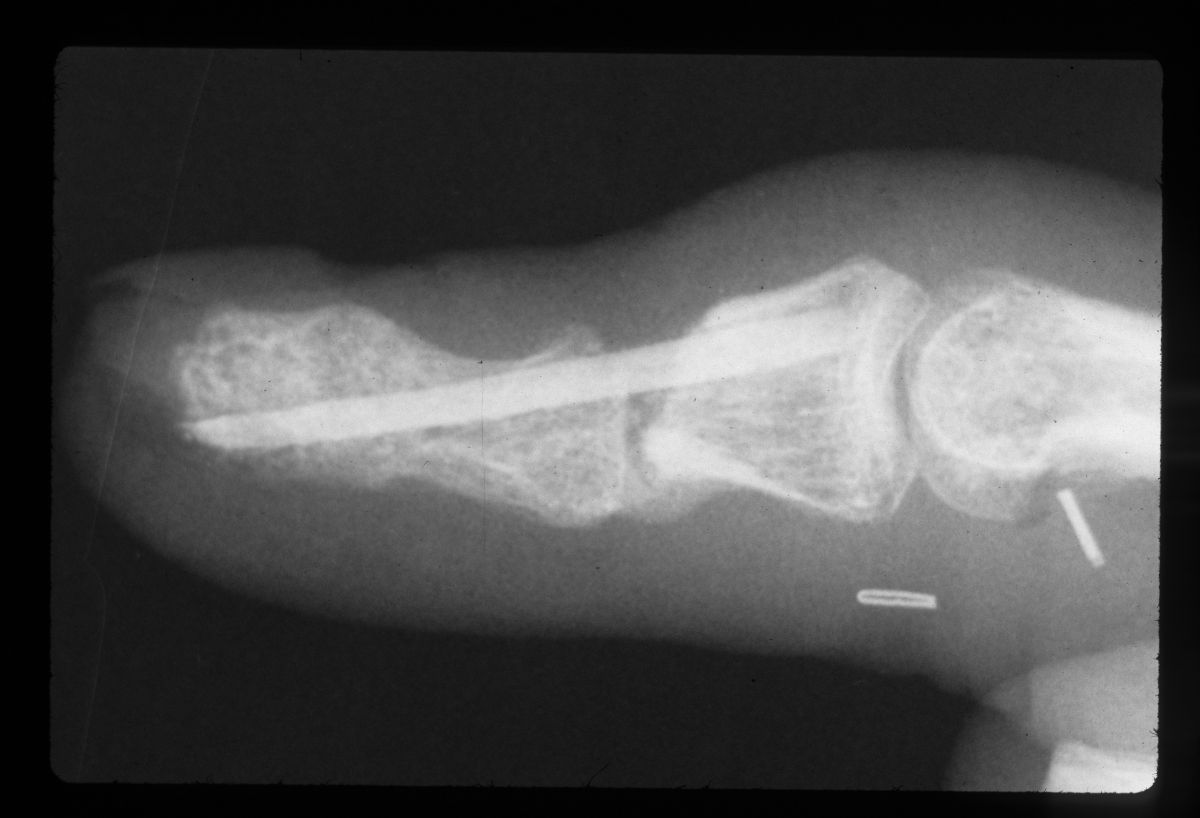

| Intraoperative films. |

| Graft in place. Exposure facilitated by using 25 gauge needles to convert a Heiss to a Gelpi retractor. |